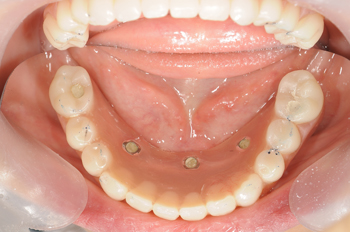

全顎オールオン4による治療

最初は義歯治療で来られた患者様です。お仕事の都合で最初は即時義歯(歯を抜いてすぐに義歯を入れる)で対応させていただきましたが、やはり年々他の歯がグラグラになり、義歯も合わなくなってきたとのことでした。そのため、全体的に治療することとなりオールオン4で治療をすることになりました。

骨の状態が少し厳しかったですが、骨盛りの治療や、メインテナンスなどでプラークコントロールを行い、無時最終の歯が入りました。新しい歯に慣れるまでに少しかかりましたが、少しずつ調整することにより、問題なく咬むことができるようになりました。

治療の内容 上下額オールオン4と骨造成による治療。

期間・回数 2年1ヶ月・20回(カウンセリング・検査・歯周病治療含む)

費用 自由診療:上下オールオン4+骨造成 総額 5,200,000円(税込 5,720,000円)